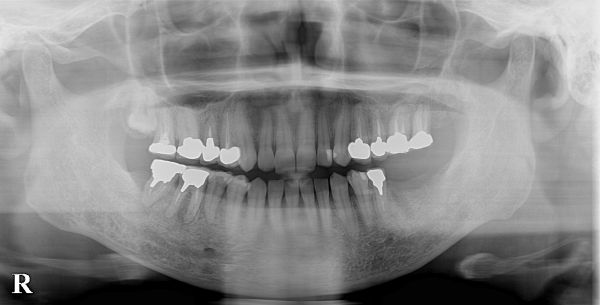

こちらが初診時のレントゲン写真となります。

左下6・7番目の歯が抜歯をされ、欠損している状態でした。